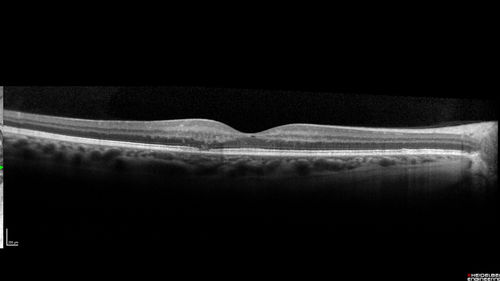

Macular Telangiectasis - Mild - Retinal Crystals

58 year old man with long term mild vision loss. Considering Cataract surgery. VA 20/50 OD and 20/63 OS - Moderate cataract are present